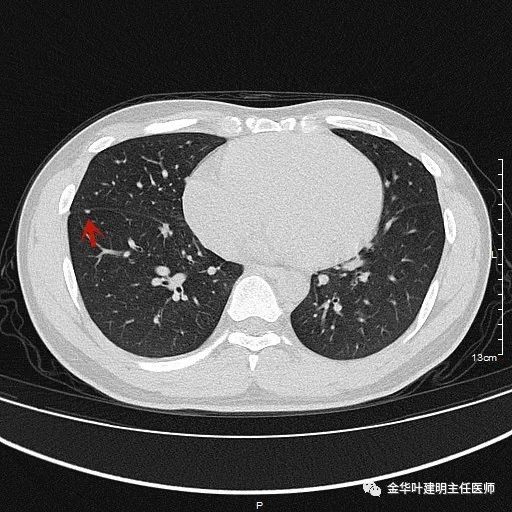

1、以下这种结节是体检发现中最常见的,它们基本上是良性的,可以年度复查:它们都是又上又实的微小结节,直径在5毫米左右或以下。实际上有许多非常焦虑的肺结节病友,他们很多人只是检查发现这种结节。我的建议是:年度复查!若实在不放心,也可半年时复查一次,以确定它不会生长。